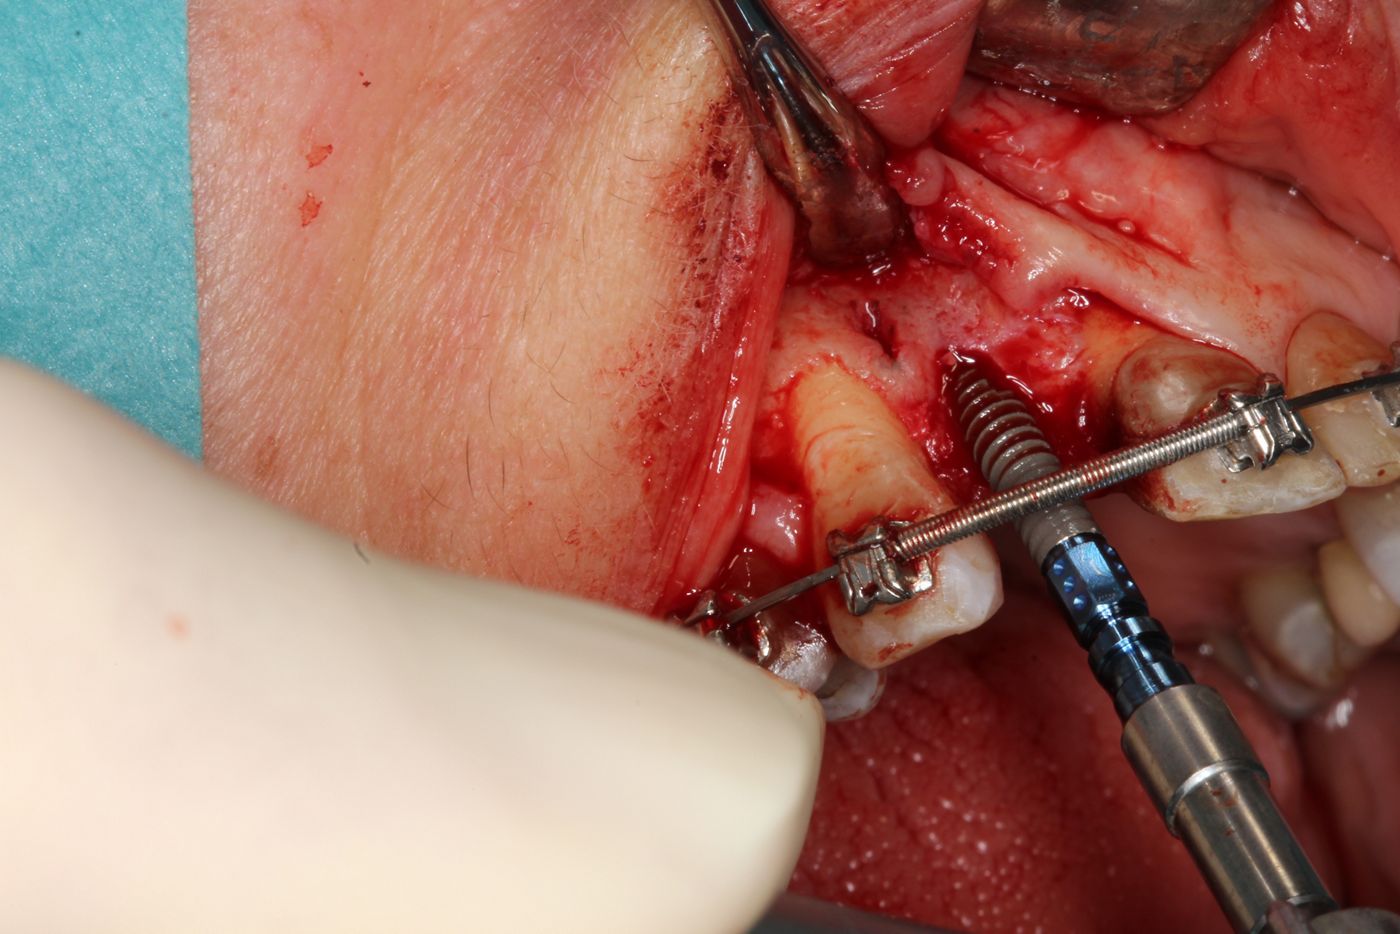

Surgical procedure

To reduce scar formation a marginal incision was made from #13 to #11, with a distal releasing incision at #13 (Figs. 4,5). The flap was deflected at the exposed bone – a narrow ridge in all dimensions (Figs. 6,7). After the pilot drilling and x-ray control of the axis (Figs. 7-9), the preparation of the implant bed was continued with the 2.2mm drill and the profile drill (Figs. 10-13). Next, the 2.9mm Straumann® BLT implant (Roxolid®, SLActive®) was inserted with a primary stability of 25Ncm, and the anatomical healing abutment was then connected (Figs. 14-18). Due to the limited bone thickness in the buccal region and a small coronal dehiscence, bone augmentation with botiss cerabone® and a Jason® membrane was also performed (Figs. 19-23). The flap was closed passively with 5-0 Prolene sutures (Figs. 24-27). The patient was prescribed antibiotics, analgesia and anti-inflammatory medication, as well as chlorhexidine rinse for 1 week. Suture removal and subsequent healing was uneventful.